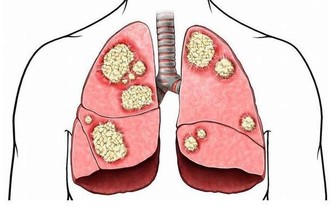

*****9.硒*****

它可以保護您的細胞免受損害和感染,並保持甲狀腺正常運轉。硒還可以保持肌肉強壯,並可以幫助預防與年齡相關的疾病,例如癡呆,某些類型的癌症和甲狀腺疾病。每天只吃一兩個巴西堅果就足夠了。不要過多,因為硒過多會使頭髮掉落並使指甲變脆。